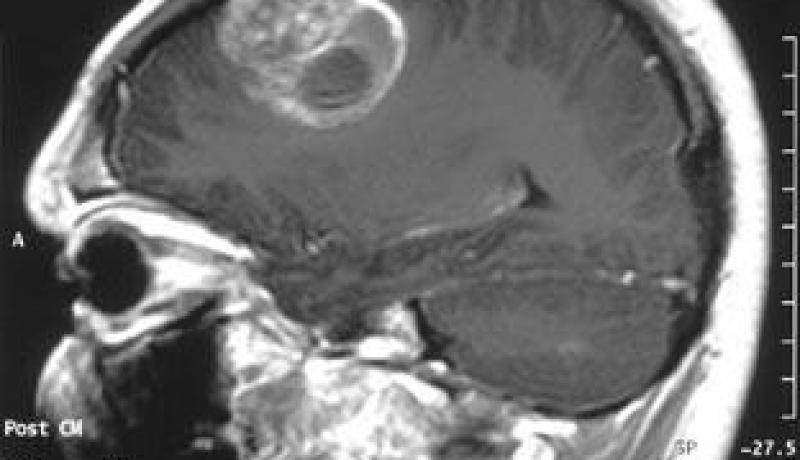

كشف رئيس جمعية طب الأورام الأستاذ كمال بوزيد اليوم السبت بالجزائر العاصمة عن تسجيل عجز في التكفل بفئة الكهول المصابين بأورام المخ مقارنة بفئة الصغار. وأكد الأستاذ بوزيد على هامش لقاء حول كيفية التكفل بأورام المخ بالجزائر بحضور خبراء من فرنسا أن فئة الأطفال المصابين بأورام المخ تحظى بتكفل أحسن مقارنة بالكهول لأن حالة الأطفال تستدعي الجراحة ثم العلاج الكميائي دون العلاج بالأشعة. وأشار نفس المختص أن التكفل بفئة الكهول المصابين بهذا الداء تتطلب الجراحة ثم العلاج بالأشعة إلا أن “قلة المراكز” التي تتكفل بهذا النوع من العلاج وابتعاد مواعيده يجعل من فرص الامتثال الى الشفاء “محدودة جدا”. وتأتي أورام المخ في المرتبة الثانية لدى الأطفال من مجموع الاصابات بالجزائر بعد سرطان الدم وفي المرتبة السابعة لدى الكهول كما يعتبر هذا النوع من السرطان من بين الأورام التي يتم الكشف عنها ب”سهولة” بالجزائر-حسب ما أكده نفس المختص–. أما رئيس مصلحة جراحة الأعصاب بالمؤسسة الاستشفائية سليم زمرلي الأستاذ بن عيسى عبد النبي فيرى من جهته أن الأورام غير الخبيثة يتم التكفل بها “جيدا” من خلال الجراحة والعلاج الكميائي وتتماثل الحالات المصابة بهذا الداء الى الشفاء. وبخصوص الأنواع الخبيثة أكد نفس المختص أنها تستدعي الجراحة ثم العلاج بالأشعة خلال الأسابيع الثلاثة الأولى التي تلي العملية الجراحية مؤكدا أن التكفل المتأخر بالعلاج بالأشعة يتسبب في تدهور حالة المريض وفشل كل مراحل العلاج التي تسبق العلاج بالأشعة. وتبقى أورام المخ التي تصيب الكهول من بين أنواع السرطان التي لاتحظى بتكفل جيد من طرف المختصين بالجزائر لكن النقص المسجل في العلاج بالأشعة يقف عائقا في وجه مختلف مراحل العلاج الأخرى–حسب الأستاذ عبد النبي–. ويتكفل مستشفى سليم زملي لوحده بأكثر من 300 حالة سرطان مخ سنويا تشمل جميع الفئات العمرية والمؤسسة الاستشفائية المتخصصة في مكافحة السرطان بيار وماري كوري بحوالي 50 حالة أورام المخ لدى الأطفال. للاشارة تسجل سنويا بين 1500 و1700 اصابة جديدة ويرى المختصون أن عدد هذه الحالات لايعكس الواقع وانما العدد الحقيقي قد يتجاوز 3500 حالة جديدة سنويا.